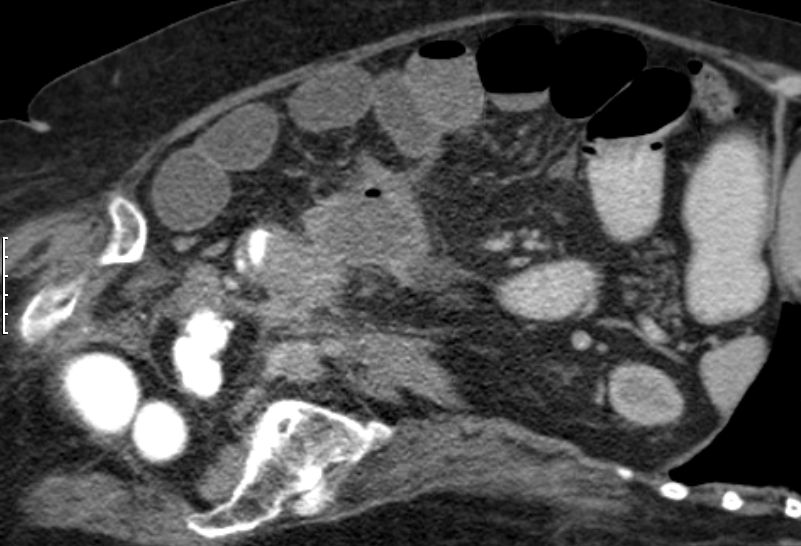

| Ileus | 78-jährige Frau in der Notaufnahme wegen Ileus. Tumor am deszendo-sigmoidalen Übergang. Hemokolektomie: Ulzeriertes Adenokarzinom pT3b pN1a (1/12)Mo L1 Vo. | ||

![]() |

![]() | |

| Ileus | Das CT zeigt einen stenosierenden Sigmatumor mit ausgeprägtem Ileus. |